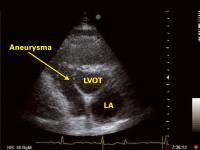

Interventrikuläres Septum - Aneurysma

Abbildung 2: Parasternaler Querschnitt auf der Ebene des linksventrikulären Ausflußtraktes: Aneurysma des interventrikulären Septums; LA = linker Vorhof; LVOT = linksventrikulärer Ausflußtrakt